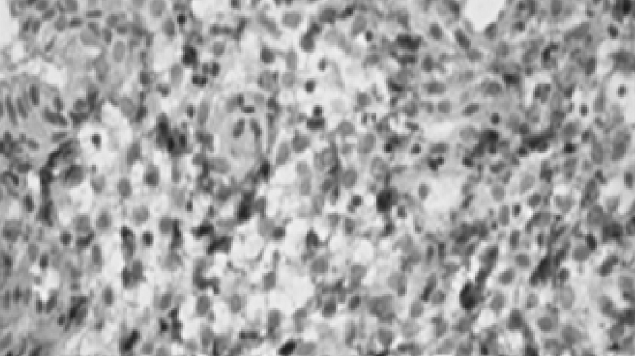

Analysis of IHC results revealed the presence of chronic endometritis with and without an autoimmune component. In terms of the receptor status of the endometrium in infertile women, chronic endometritis was accompanied by a decrease in ER expression in the glands in both the proliferative and secretory phases, but was mainly in the secretory phase in the stroma (Figure 1). PR expression in the glands and endometrial stroma decreases in the secretory phase (Figure 2).

Fig. 1. Estrogen receptors